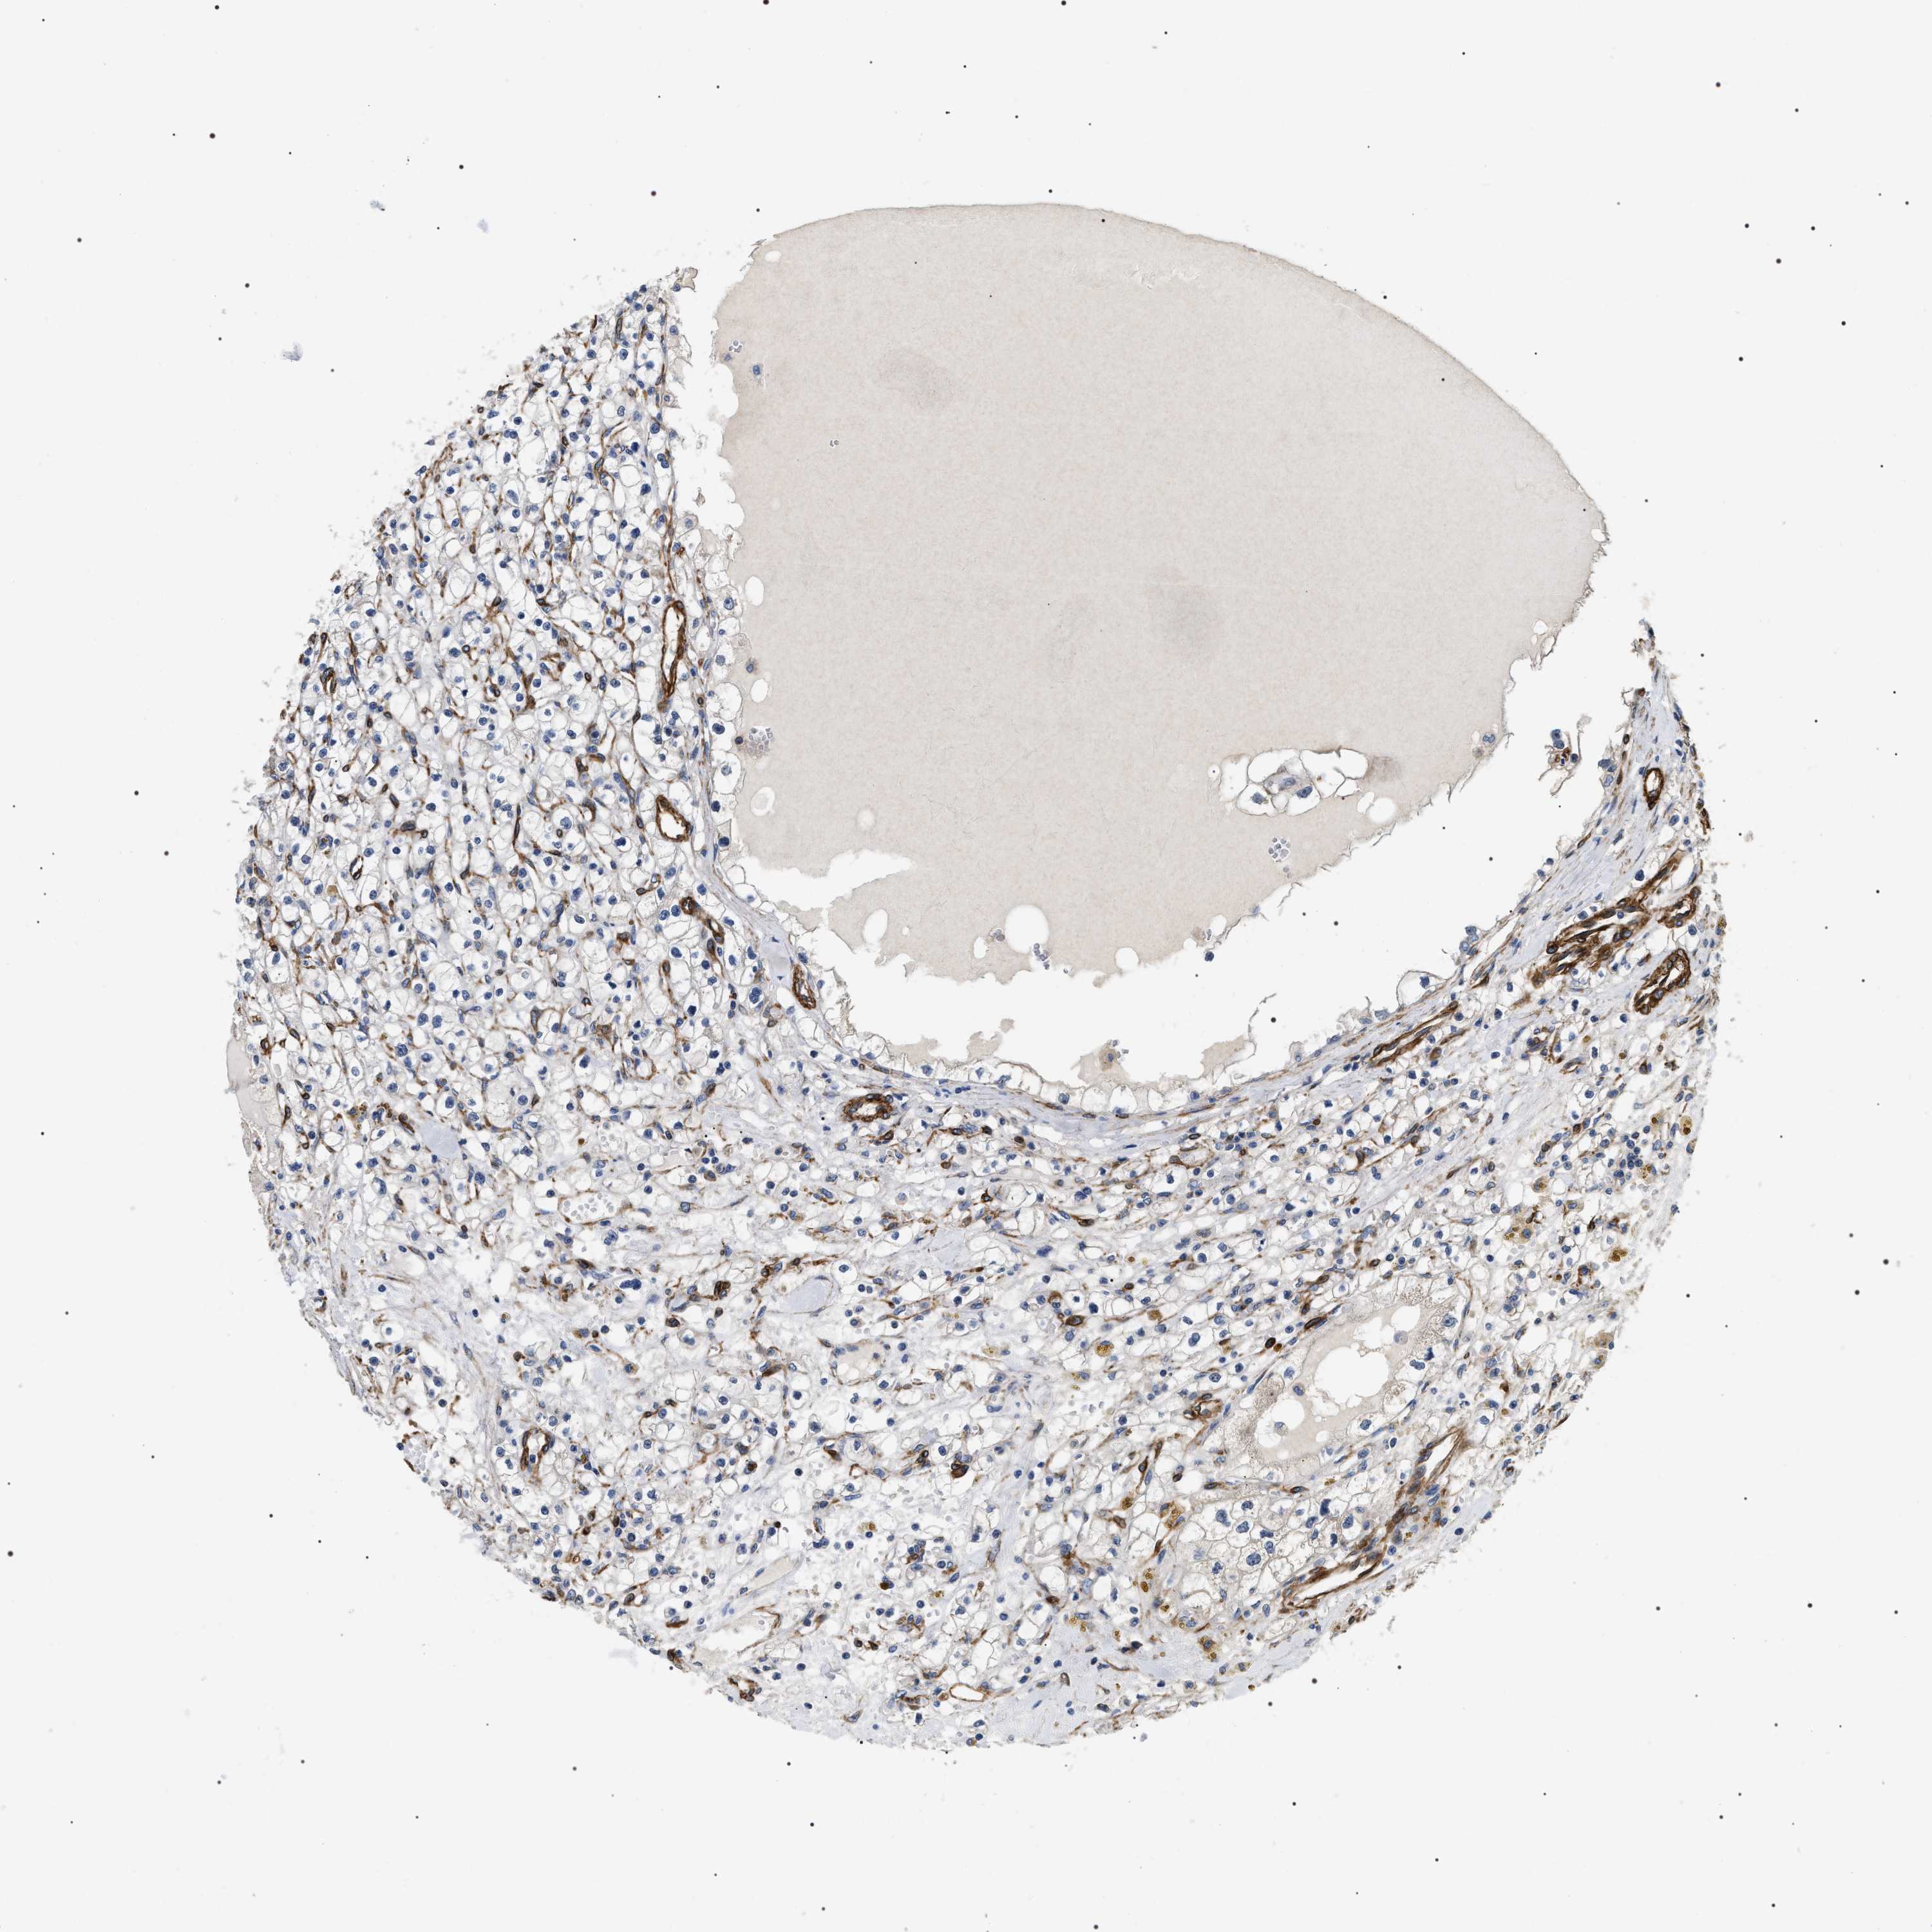

KIDNEY RENAL PAPILLARY CELL CARCINOMA (TCGA) - Interactive survival scatter ploti

The Survival Scatter plot shows the clinical status (i.e. dead or alive) for all individuals in the patient cohort, based on the same data that underlies the corresponding Kaplan-Meier plots. Patients that are alive at last time for follow-up are shown in blue and patients who have died during the study are shown in red.

The x-axis shows the expression levels (FPKM) of the investigated gene in the tumor tissue at the time of diagnosis. The y-axis shows the follow-up time after diagnosis (years). Both axes are complimented with kernel density curves demonstrating the data density over the axes. The top density plot shows the expression levels (FPKM) distribution among dead (red) and alive patients (blue). The right density plot shows the data density of the survived years of dead patients with high and low expression levels respectively, stratified using the cutoff indicated by the vertical dashed line through the Survival Scatter plot. This cutoff is automatically defined based on the FPKM cutoff that minimizes the p-score. The cutoff can be changed by dragging the vertical line or by entering a cutoff value in the square labeled "Current cut-off".

Under the Survival Scatter plot the p-score landscape (black curve; left axis) is shown together with dead median separation (red curve; right axis). Dead median separation is the difference in median mRNA expression between patients who have died with high and low expression, respectively. It is calculated as follows: median FPKM expression of dead patients with high expression - median FPKM expression of dead patients with low expression. This is intended to aid the user in visually exploring custom cutoffs and the associated p-scores and dead median separation.

Individual patient data is displayed and can be filtered by clicking on one or more of the category buttons on the top of the page. Categories describing expression level and patient information include: high, low, alive, dead, female, male and tumor stages. The scale of the x-axis can be toggled between linear and log-scale by clicking on the "x log" button. Mouse-over function shows TCGA ID, patient information and mRNA expression (FPKM) for each patient.

& Survival analysisi

Kaplan-Meier plots summarize results from analysis of correlation between mRNA expression level and patient survival. Patients were divided based on level of expression into one of the two groups "low" (under cut off) or "high" (over cut off). X-axis shows time for survival (years) and y-axis shows the probability of survival, where 1.0 corresponds to 100 percent.

ZC3HAV1L is not prognostic in Kidney Renal Papillary Cell Carcinoma (TCGA)